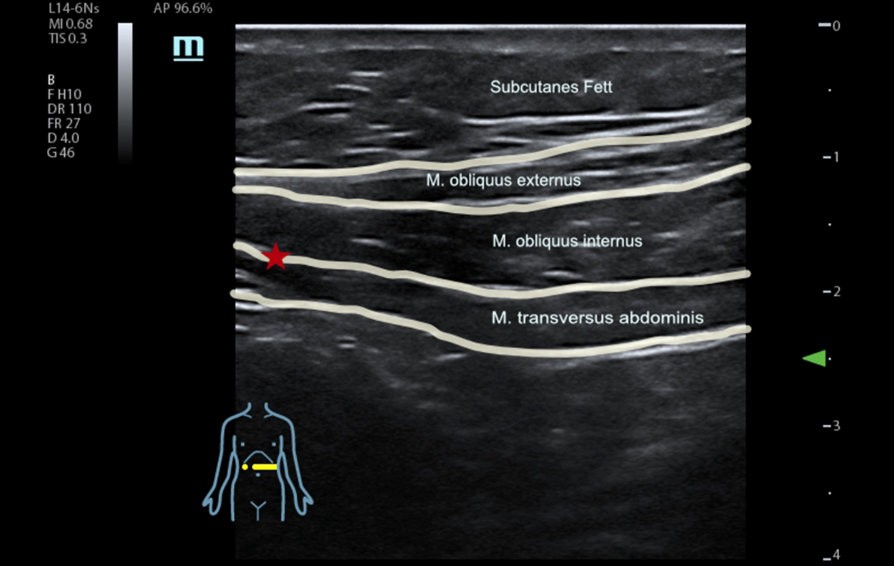

![switch-off-pain-ultrasound-controlled-trunk-blocks.thumb.1280.1280 Schmerz abschalten mit ultraschallgesteuerten Rumpfblockaden]() Ultraschall | An?sthesieSchmerz abschalten mit ultraschallgesteuerten Rumpfblockaden

Ultraschall | An?sthesieSchmerz abschalten mit ultraschallgesteuerten Rumpfblockaden -